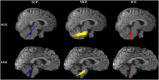

Background: Spinocerebellar ataxia type 3/Machado-Joseph disease (SCA3/MJD) is one of the nine polyglutamine (polyQ) diseases and is caused by a CAG repeat expansion within the coding sequence of the ATXN3 gene. Few multimodal imaging analyses of the macro- and micro-structural changes have been performed. Methods: In the present study, we recruited 31 genetically-confirmed symptomatic SCA3/MJD patients and 31 healthy subjects as controls for a multimodal neuroimaging study using structural magnetic resonance imaging (sMRI), proton magnetic resonance spectroscopy (1H-MRS) and diffusion tensor imaging (DTI). Results: The SCA3/MJD patients displayed a significantly reduced of gray matter volume in the cerebellum, pons, midbrain and medulla, as well as inferior frontal gyrus and insula, and left superior frontal gyrus. The total International Cooperative Ataxia Rating Scale (ICARS) score was inversely correlated with the gray matter volume in the cerebellar culmen, pons and midbrain. The numbers of CAG repeats in the expanded alleles were inversely correlated with the gray matter in the cerebellar culmen. NAA/Cr and NAA/Cho ratio in the middle cerebellar peduncles, dentate nucleus, cerebellar vermis, and thalamus in the SCA3/MJD patients were significantly reduced when compared to that in the normal controls, suggesting neurochemical alterations in cerebellum in the SCA3/MJD patients. Tract-Based Spatial Statistics (TBSS) analysis revealed significant lower volume and mean FA values of the cerebellar peduncles, which inversely correlated with the total scores of ICARS in our patients. Conclusions: In this study, we demonstrated cerebellar degeneration in SCA3/MJD based on tissue volume, neurochemistry, and tissue microstructure. Moreover, the associations between the clinical measures, cerebellar degeneration and genetic variation support a distinct genotype-phenotype relationship in SCA3/MJD.